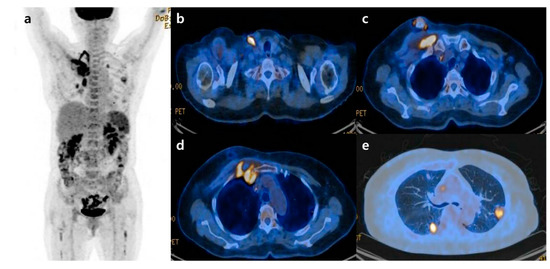

Figure 1. A chest X-ray was performed at admission, showing scattered nodular opacities in the left lung upper lobe and right lung lower lobe, which indicated a central area of excavation (arrows). 18F-fluorodeoxyglucose positron emission tomography/computed tomography (18F-FDG PET/CT) has increasingly been used to manage cancers and infections [1,2,3]. Since FDG uptake is directly representative of glucose metabolism, it can increase in inflammatory cells as well as tumor cells. Long-term indwelling central venous catheters are necessary for treating cancer patients due to chemotherapy. They depend on their central venous catheters daily, which could predispose a significant risk of complications such as catheter-related bloodstream infection (CRBSI) [4,5,6]. CRBSI can be complicated by metastatic infectious foci associated with a high morbidity and mortality rate, which should require prolonged systemic antimicrobial treatment [7]. The significant complication of CRBSI is septic thrombosis, with a prevalence of 15~24% [8,9]. The clinical diagnosis of septic foci is critical but may be difficult to establish due to the challenge of determining between sterile catheter-related thrombosis and actual septic thrombosis. Additionally, symptoms are often non-specific, and there is a lack of sensitivity to conventional diagnostic imaging techniques. Only a few studies investigated that 18F-FDG PET/CT can find the infectious foci, demonstrating it as an accurate imaging modality for metastatic foci [10,11,12]. Here, we would like to report a female patient with a Staphylococcus aureus-implantable venous access catheter infection in which 18F-FDG PET/CT determined unsuspected septic pulmonary emboli. A 71-year-old female patient with known ovarian cancer visited our hospital to receive the 4th adjuvant chemotherapy. She was treated with total abdominal hysterectomy, bilateral salpingo-oophrectomy and omentectomy 6 months ago. She also had a history of central venous catheterization by the right internal jugular vein approach, terminating at the junction of the superior vena cava and right atrium. The adjuvant chemotherapy was already performed three times as the regimen of Paclitaxel plus Carboplatine after surgery. At admission, she presented no clinical symptoms such as fever, cough, sputum, dyspnea, or chest pain. However, the chest X-ray showed scattered nodular opacities in the left lung upper lobe and right lung lower lobe, suspicious of metastatic nodules (Figure 1). Her blood test showed unexplained leukocytosis (12.58 × 103/μL), elevated D-dimer (9.46 mg/L), and a tumor marker such as CA-125 (41.89 U/mL). 18F-FDG PET/CT was performed 2 days after admission, observing abnormal FDG uptake in the chemo-port catheter, right pectoralis muscle, and 1st costochondral junction (Figure 2a–d). PET/CT also revealed hypermetabolic nodules scattered throughout both lungs, consistent with septic embolism (Figure 2e). In the evening of the day of the PET/CT examination, the patient presented swelling, redness, and some discomfort at the catheter insertion site. The catheter was removed the next day, isolating methicillin-sensitive Staphylococcus aureus from the catheter tip and peripheral vein. A transthoracic echocardiogram and fundus examination, which were performed to evaluate possible metastatic infections such as infective endocarditis or endophthalmitis, were reported as normal. She was treated with intravenous cefazolin for 4 weeks followed by oral linezolid for 1 week, recovering uneventfully without relapse. She was also treated with rivaroxaban 15 mg for 3 weeks and was diagnosed with pulmonary thromboembolism. After 2 months, a follow-up chest CT showed that the pre-existing multiple nodules in both lungs had disappeared (Figure 3).

Figure 2. 18F-FDG PET/CT images (a) showed abnormal FDG uptake in the chemo-port catheter (b), right pectoralis muscle (c), and the anterior thoracic wall around the first costochondral junction, consistent with an inflammatory/infectious process (d). Lung window setting image, showing multiple cavitating hypermetabolic nodules in both lungs consistent with septic pulmonary emboli (e). According to these findings, the patient was suspected of having catheter-related bloodstream infection and septic pulmonary emboli.

Figure 3. Follow-up chest CT after intravenous antibiotic treatment. A representative axial image reveals complete resolution of the lung lesions that were observed in the earlier PET/CT scan. Discussion Although 18F-FDG PET/CT has achieved great success in investigating malignant disorders, the imaging modality is not only specific for cancer diagnosis [13]. Since the activated inflammatory cells showed an increased expression and up-regulation of glucose transport receptors, several studies have reported the presence of high FDG uptake in acute and chronic infectious diseases such as mycobacterial, fungal, bacterial infection, sarcoidosis, radiation pneumonitis, and postoperative inflammation [14,15,16]. In this case report, we evaluated the utility of 18F-FDG PET/CT in a patient with a suspected metastatic infectious disease, and showed that it can visualize the correct foci leading to therapeutic management. CRBSI is associated with significant morbidity due to systemic infection and causes septic pulmonary emboli, which originate from the extrapulmonary site transported to the lung [17]. Like this case, clinical symptoms of septic pulmonary emboli are usually non-specific, and an active extrapulmonary focus of the infection might be apparent at the time of presentation, especially in cancer patients on chemotherapy via an indwelling central venous catheter for long durations. In conclusion, 18F-FDG PET/CT can detect septic pulmonary emboli in patients with catheter-related Staphylococcus aureus bacteremia. This case report suggests that cancer patients with CRBSI might benefit from 18F-FDG PET/CT for a timely evaluation of metastatic infection and optimal management. In accordance with previous studies suggesting the clinical value of 18F-FDG PET/CT in patients with Gram-positive bacteremia [5,10,11,18,19,20], we believe that the benefit from 18F-FDG PET/CT might be mediated by infective foci detection, earlier interventions to control infection, and the prolongation of antimicrobial treatment.